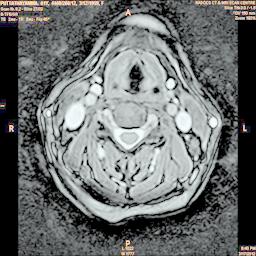

The developed algorithm presented in the previous section was coded using Matlab Version 8.0. The experiment was conducted by considering poor quality spinal cord images of having various lesions. The first column of Fig. 4 shows the axial view of neck spinal cord images of size pixels, respectively. The second column of Fig. 4 presents the same images enhanced using histogram equalization. As is evident from the results presented, the histogram equalization method performs global image enhancement operation which improves the contrast of an image but at the cost loss in image details. The third column of Fig. 4 shows the MSR based spinal cord image enhancement. It can be seen that from the result presented, MSR scheme improves the details that are not clearly visible in histogram equalization technique. In general, image enhancement achieved by MSR method is better compared to histogram equalization. However, the MSR method voilates gray world assumption. Therefore, the image enhanced by this scheme appears to be grayish. Although, numerous work have been reported for solving the problem due to gray world voilation, no work seems to developed for complete elimination.

The fourth column of Fig. 4 shows the image enhanced using Chao et al. []. It can be seen from the results presented that the reconstructed images of Chao’s method have black spots. The appearance of these dark patches degrades the visual quality of the enhanced image. The image enhanced using proposed multirate multiscale retinex image enhancement method presented in the fifth column of Fig. 4, overcomes the drawback of the Chao’s method. As we can see from the simulation results, image enhancement achieved by the proposed method has improved details with significant contrast enhancement. The enhanced images from the proposed method provides information to physicians, radiologists and researchers for various types of pathology detection.